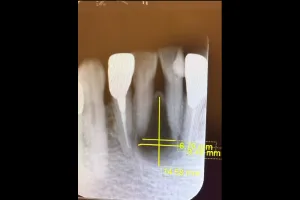

Case.01

治療前

治療中

治療後

治療前後の比較

| 治療名 | 根管治療 |

| 患者様情報 | 76歳 女性 |

| 担当医 | 岸田 義弘 先生 |

| 費用 | 1根管33,000円~ |

| 主訴 | 下の前歯の歯茎が腫れて痛い |

| 治療期間 | 約2ヶ月 (月1〜2回) |

| 治療内容 | 1.歯髄が生きているかどうかの確認 2.根管治療 3.修復治療 4.経過観察 治療の結果腫れもなくなり、歯の移動も戻りました。 |

| 治療のリスク | 術後2~3日後に痛みが出ることあります。術後1年程経過を追って、治癒傾向があれば経過観察、病変の拡大を認めるならば外科的対応になる可能性があります。 |